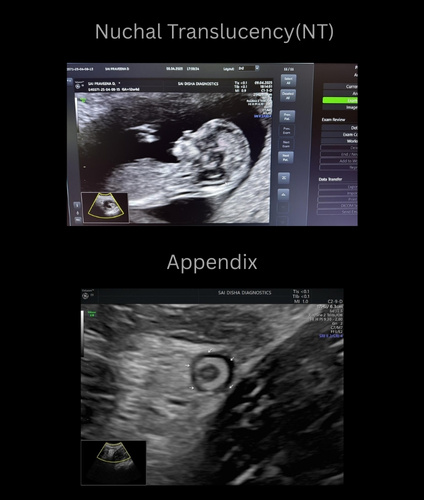

An ultrasound scan, also known as sonography, is a safe and non-invasive diagnostic procedure that uses sound waves to produce real-time images of the inside of the body. Unlike X-rays or CT scans, ultrasound does not use any radiation, making it especially suitable for monitoring pregnancies and for routine diagnostic imaging. During the procedure, a special gel is applied to the skin, and a device called a transducer is gently moved over the area of interest. The sound waves travel into the body and bounce back to create clear images of organs, tissues, and blood flow and fetus inside pregant mother.

Sai Disha Diagnostics offers high-resolution ultrasound imaging to support early and precise diagnosis across a wide range of medical conditions.